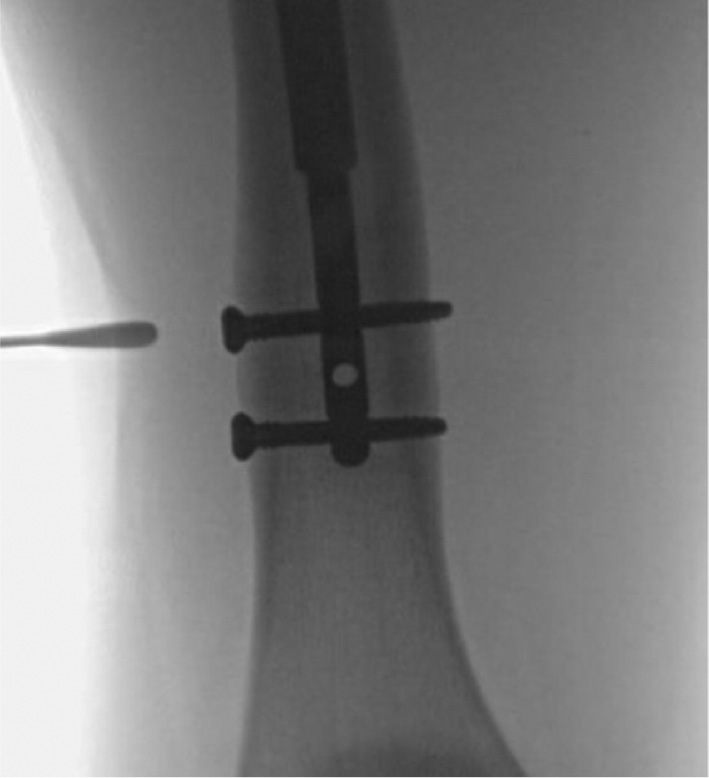

Figure 12. Fluoroscopic image demonstrated the threaded retrieval device capturing the proximal portion of the nail.

jposna20220031_fig12.jpg

Figure 13. A cannulated impactor is attached to the threaded retrieval device.

jposna20220031_fig13.jpg